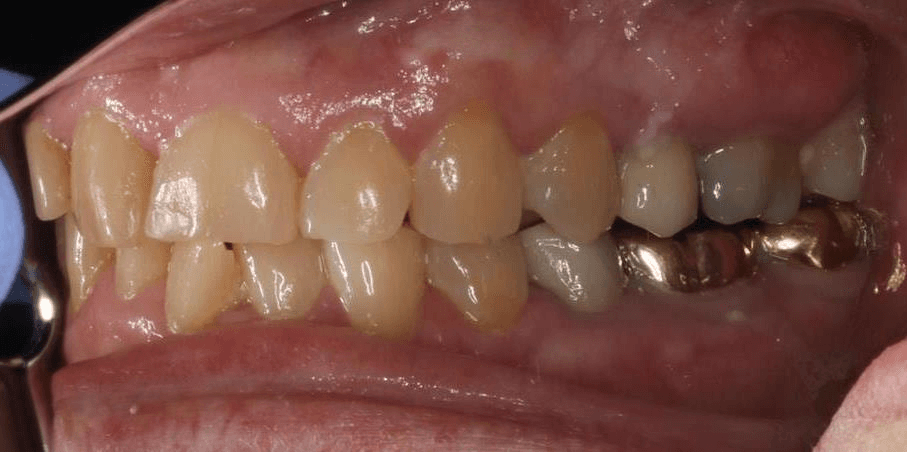

INTRAORAL